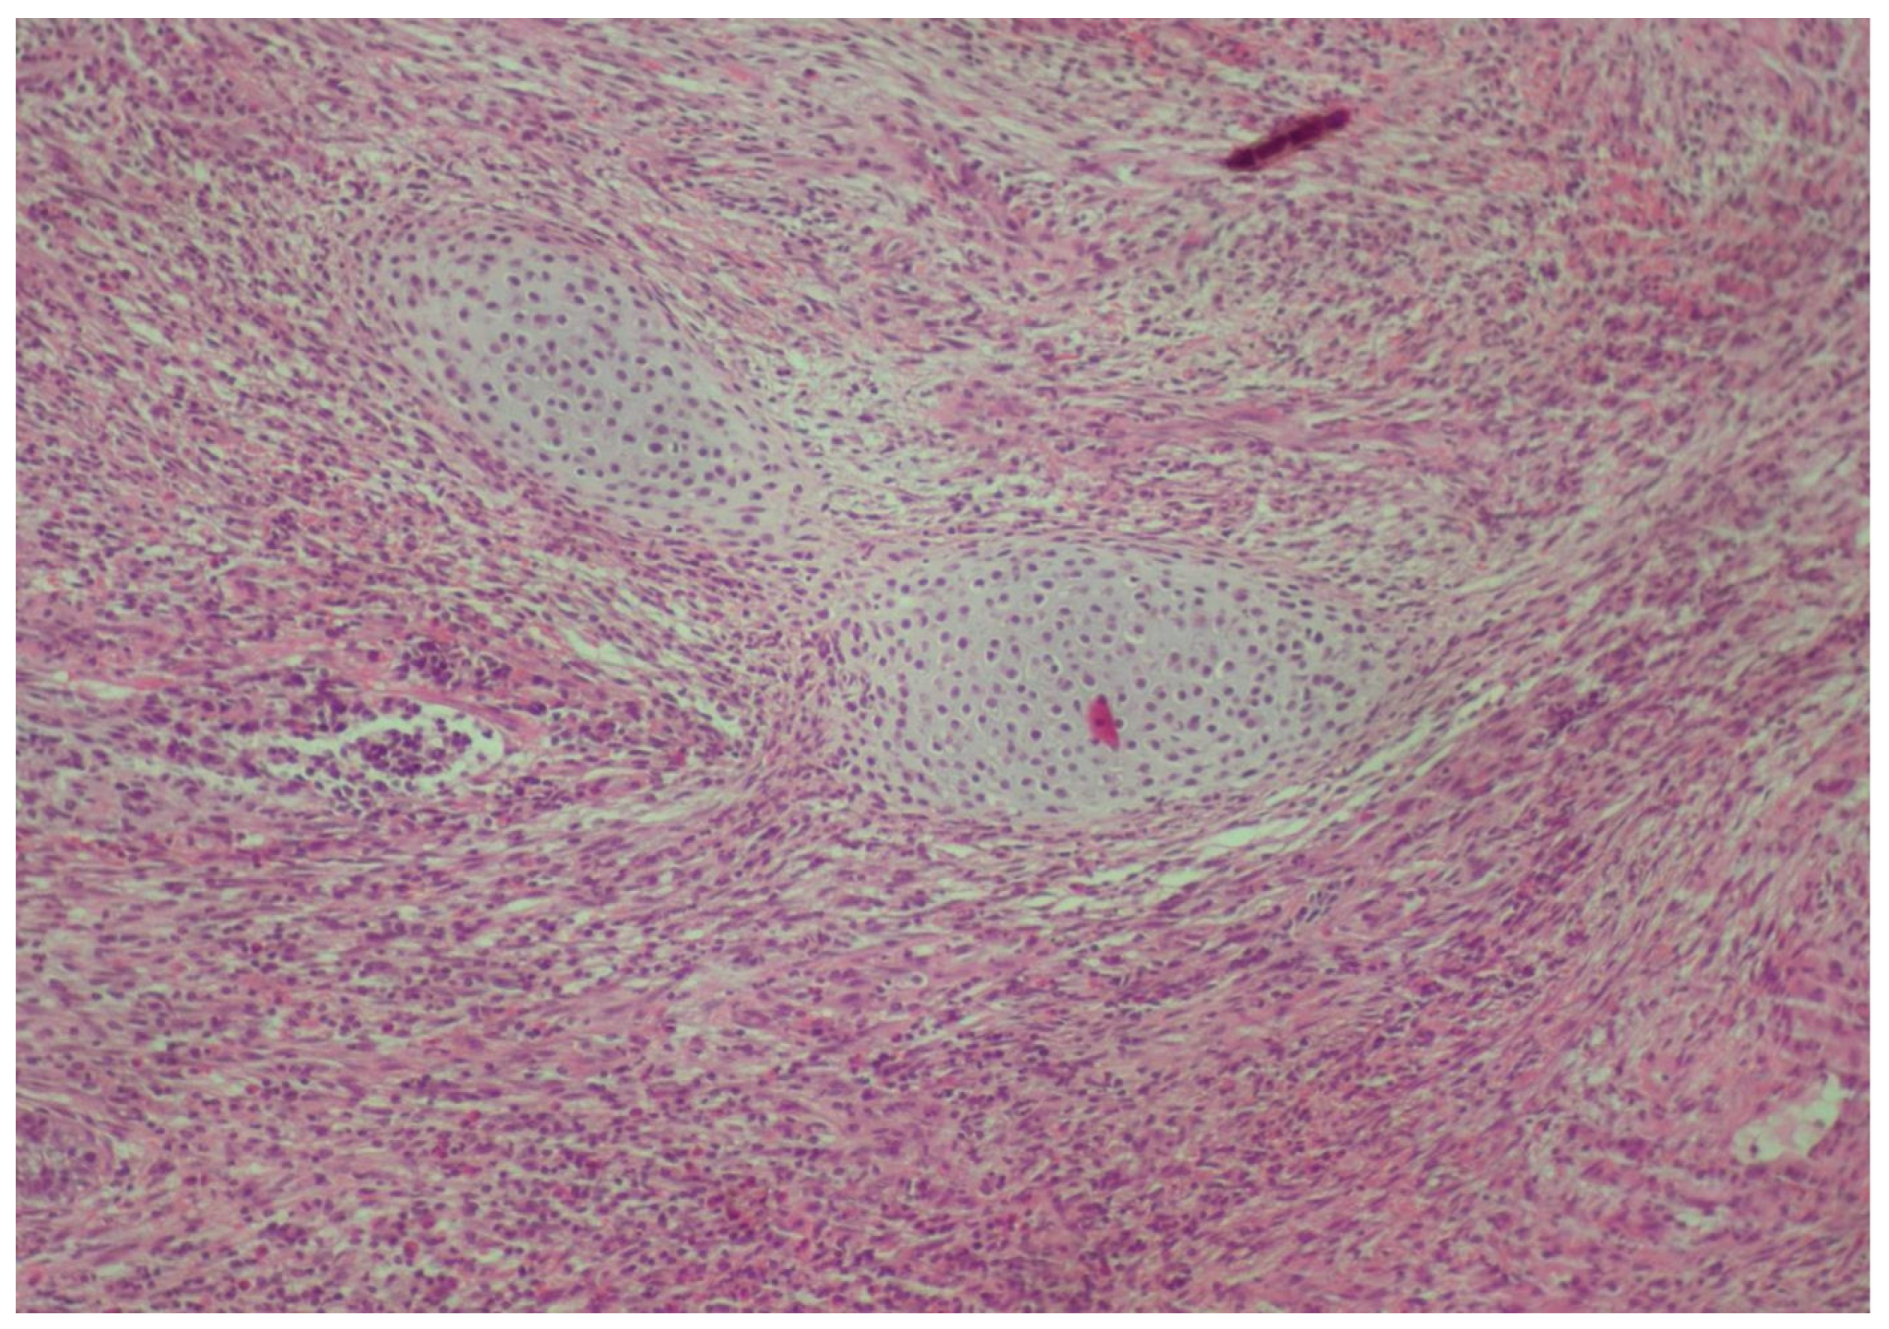

2. Case Presentation